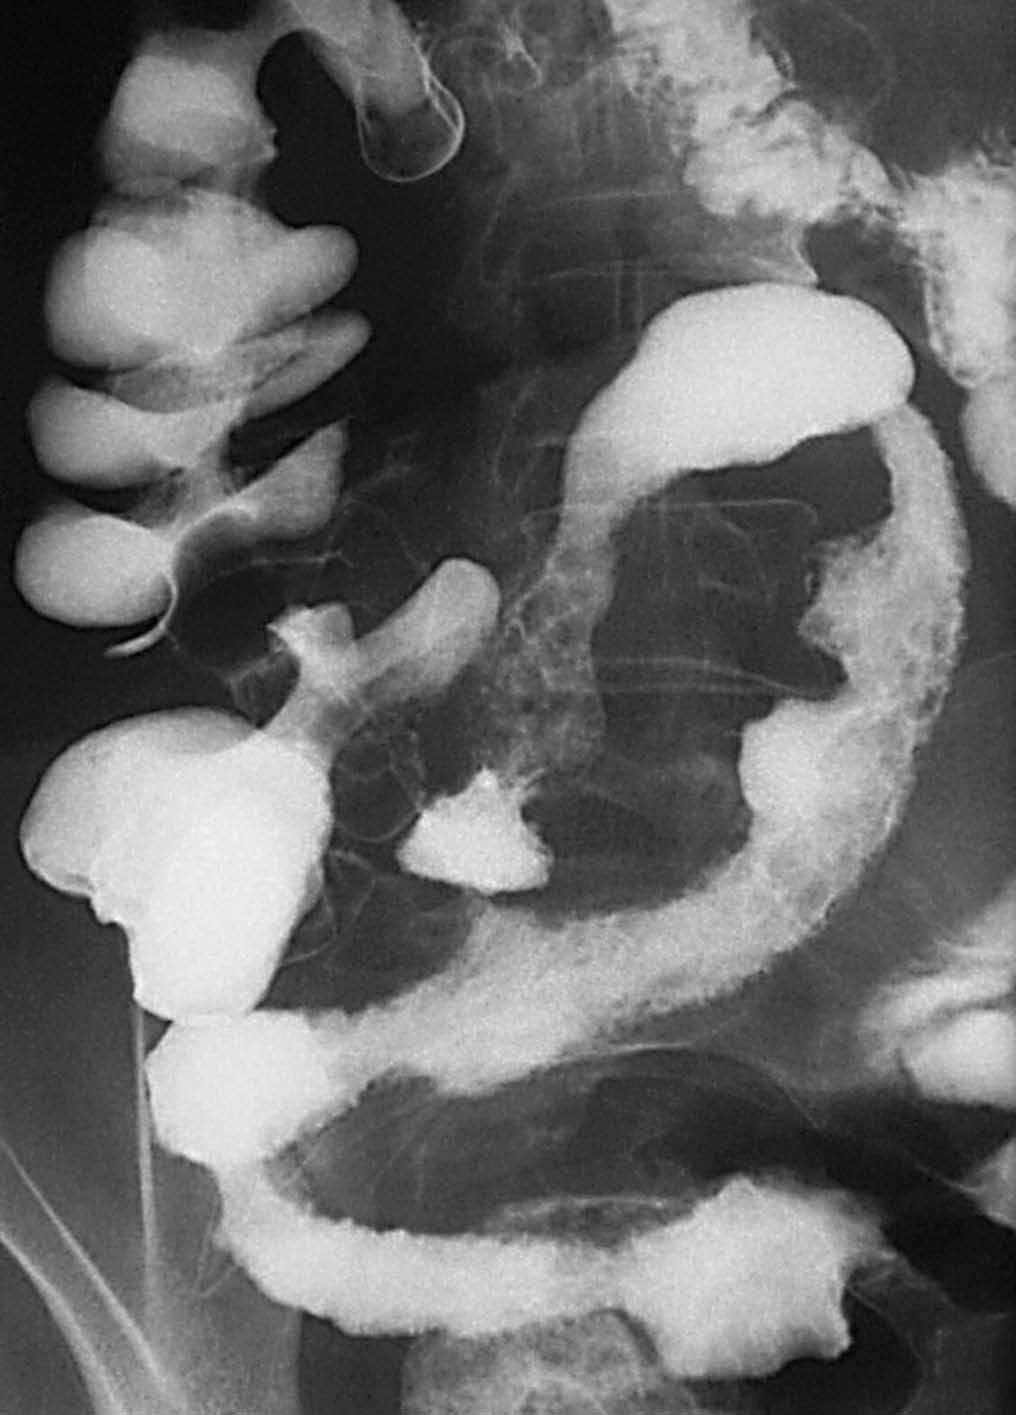

En la fase activa hay presencia de úlceras superficiales o aftoides (fig. 4). Pueden evolucionar haciéndose ulceraciones fisurantes longitudinales y transversales, dejando entre sí islotes de mucosa normal, constituyendo el concepto de patrón en "empedrado" (fig. 5).

Fig. 5.--Enfermedad de Crohn, fase activa inflamatoria. (A) Ulceraciones longitudinales y transversales que dejan entre sí islotes de mucosa edematosa, constituyendo el patrón en "empedrado" en el estudio baritado. (B) Correlación microscópica: ulceración fisurante rodeada del infiltrado inflamatorio, lesión claramente delimitada y rodeada de mucosa normal.